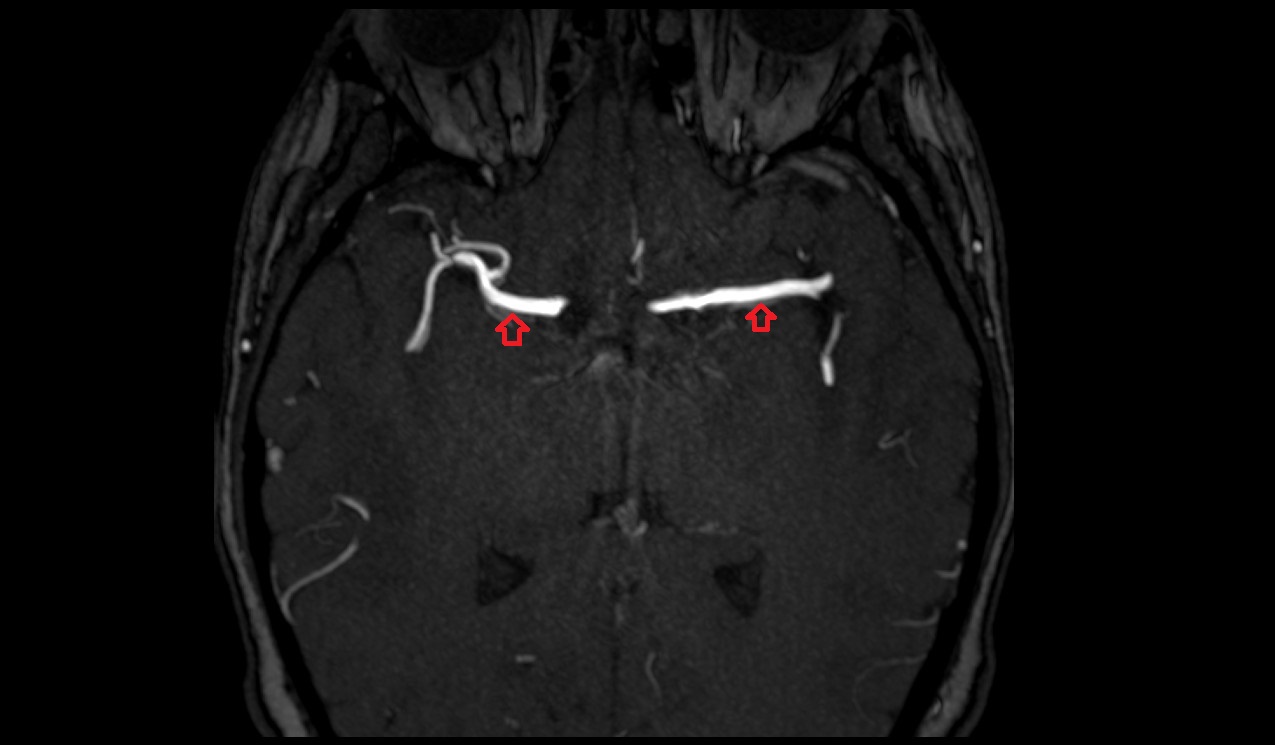

- Transverse sinus

- Superior sagittal sinus

- Sigmoid sinus